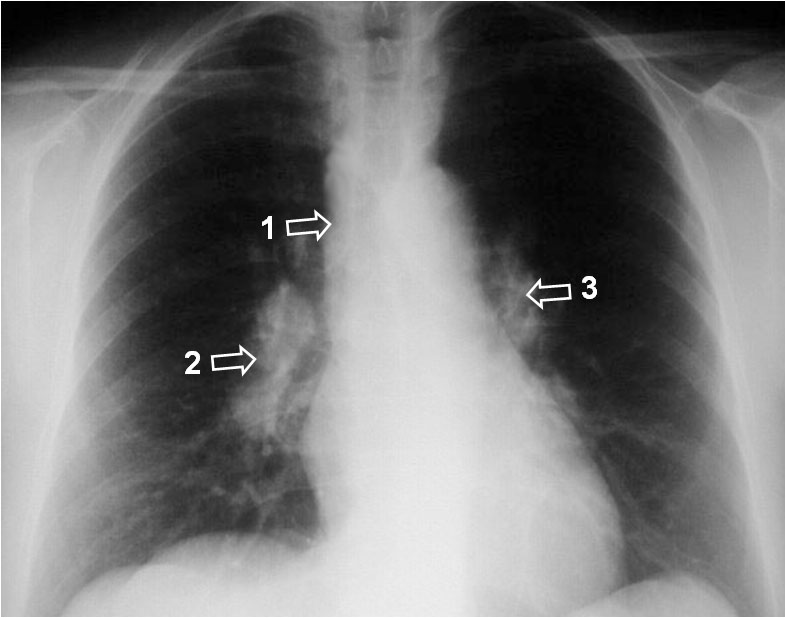

SIGNO UN-DOS-TRES, SIGNO DE PAWNBROKERS O TRIADA DE GARLAND

La presencia de adenopatías en el espacio paratraqueal derecho (uno) y en ambos hilios (dos-tres) se ha descrito como un signo característico de la afectación ganglionar por sarcoidosis, visible hasta en un 85 % de pacientes en estadio I. Además, estas adenopatías se diferencian de las del linfoma por estar más separadas de la silueta cardiomediastínica (como se ve en la imagen, especialmente en el lado derecho) ya que son adenopatías bronquiales, mientras que las del linfoma son propiamente hiliares y están unidas a la silueta cardiomediastínica.